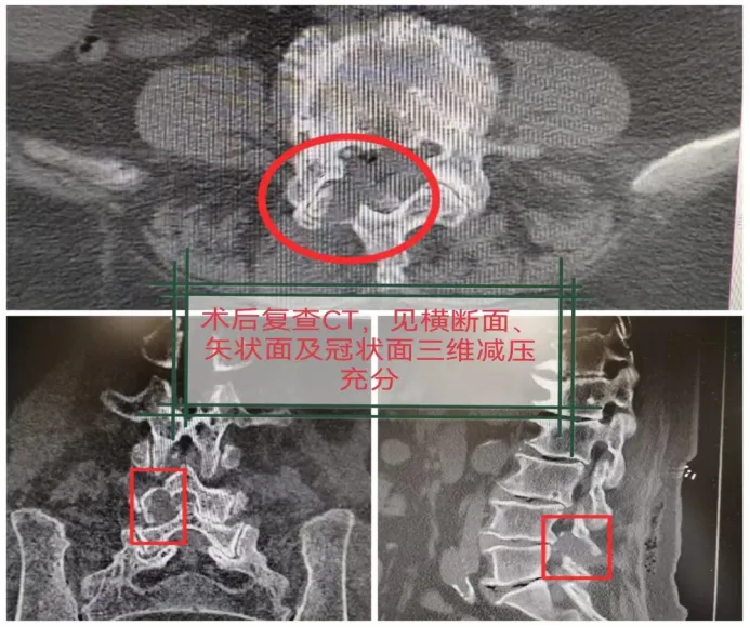

图5 术后第一天复查腰椎CT,见横断面、矢状面及冠状面三维减压充分